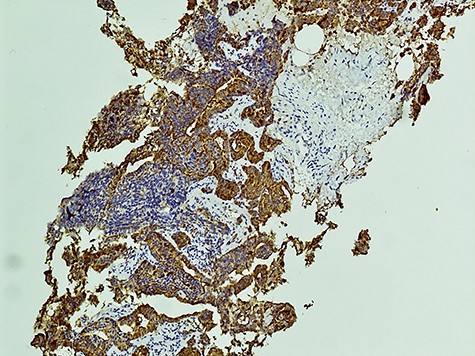

The diagnosis of SCCP is based on morphological features defined in the World Health Organization (WHO) classification criteria of pulmonary neoplasms (WHO 2015). From a diagnostic point of view, it is important to recognize this rare variant and not misdiagnose it for a high-grade Gleason 5 pattern, as there is a morphological overlap [5]. In cases where there is morphologic concern for neuroendocrine carcinoma (sheet-like architecture, nuclear molding and scant cytoplasm), it is essential to perform immunohistochemistry with neuroendocrine markers and PSA. In our case, the SCC component was strongly positive for neuroendocrine markers Synaptophysin and CD56 with focal positivity for PSA. In the conventional component it was the reverse; strong PSA positive and very focal NE scattered cells (Figs 3 and 4). This is in line with the literature findings [5, 8].